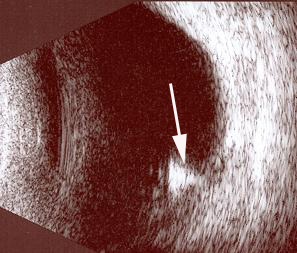

Resim 4: Retinadaki yabancı cismin ultrasonografi görüntüsü. Altta, yabancı cisme ait beyaz refle görülmektedir (beyaz oklar).